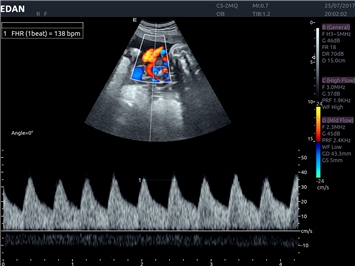

• Акушерства и гинекологии

Импульсно-волновой допплер:

Да

Триплексное сканирование:

3D/4D: